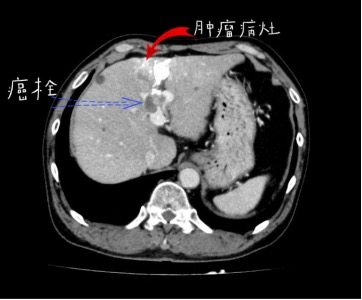

2019年4月,患者就诊于外院,经CT检查,考虑肝细胞癌合并门脉左支癌栓形成、腹腔淋巴结转移。

2019年12月行肝脏影像学检查提示门脉栓子形成,经系统检查诊断:

患者术前CT